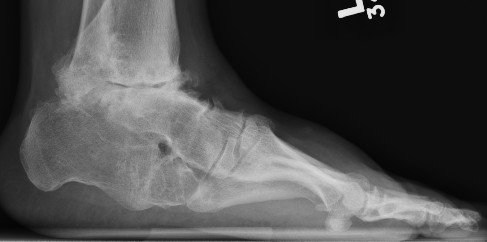

Planovalgus secondary to rheumatoid arthritis